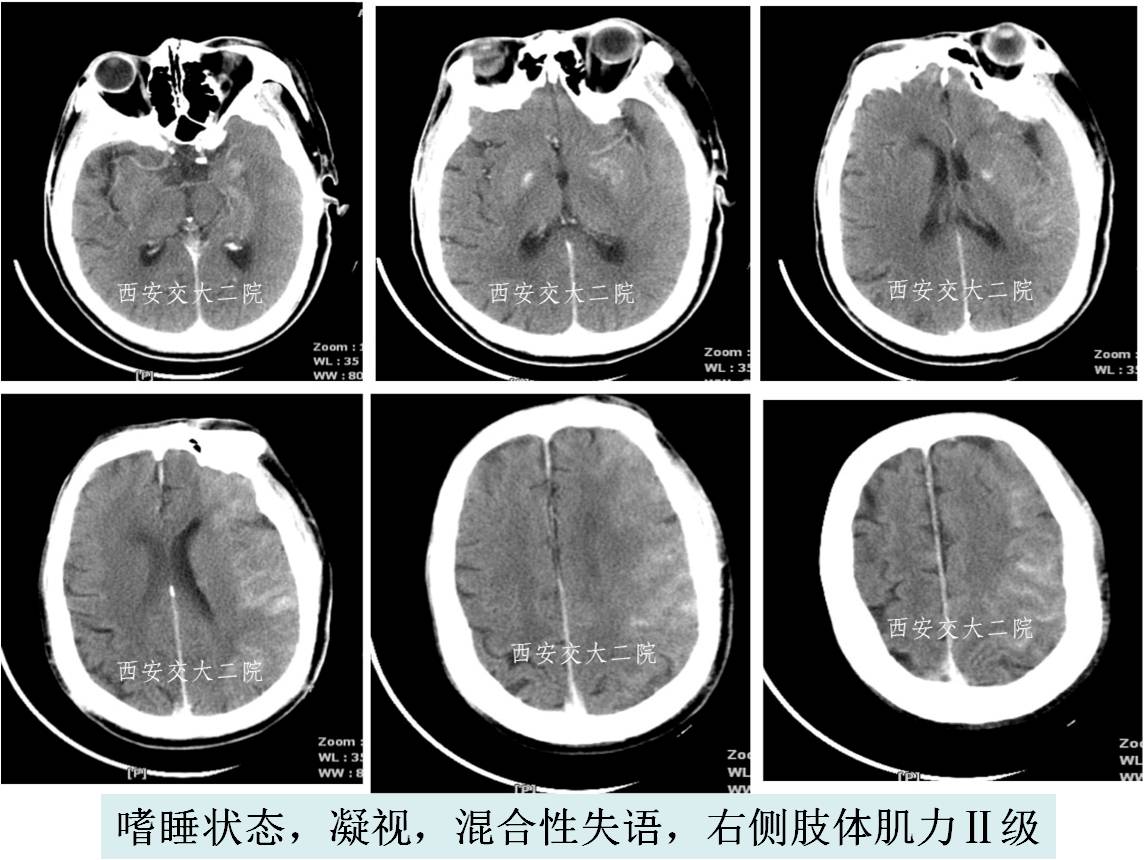

Case 3 大脑中动脉急性闭塞取栓术

》67岁,男;

》有房颤病史,2013.11.25于我院心内住院;

》突然意识不清、左侧肢体瘫痪,言语不能1h;

》查体:嗜睡,混合性失语,双眼向左凝视,双侧瞳孔形圆等大,直径约3mm,对光反射灵敏,右侧肢体肌力0级。

急诊脑CT

取栓后即刻脑CT及临表

术后24h脑CT及临表

术后4天脑CT及临表

术后2周脑CT及临表